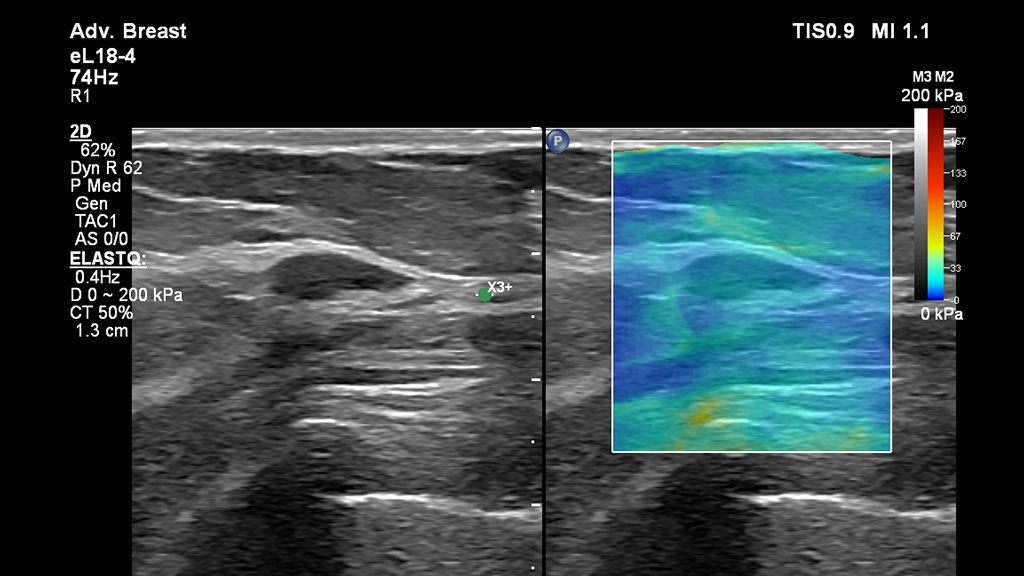

• Breast Mass

As demonstrated with the eL18-4 Transducer, Strain Elastography is a non-invasive, real-time imaging technique that displays an overlay of stiffness information over a greyscale 2D image.

• ElastQ Imaging shear wave and strain elastography reveal more definitive information on tissue stiffness in the breast.